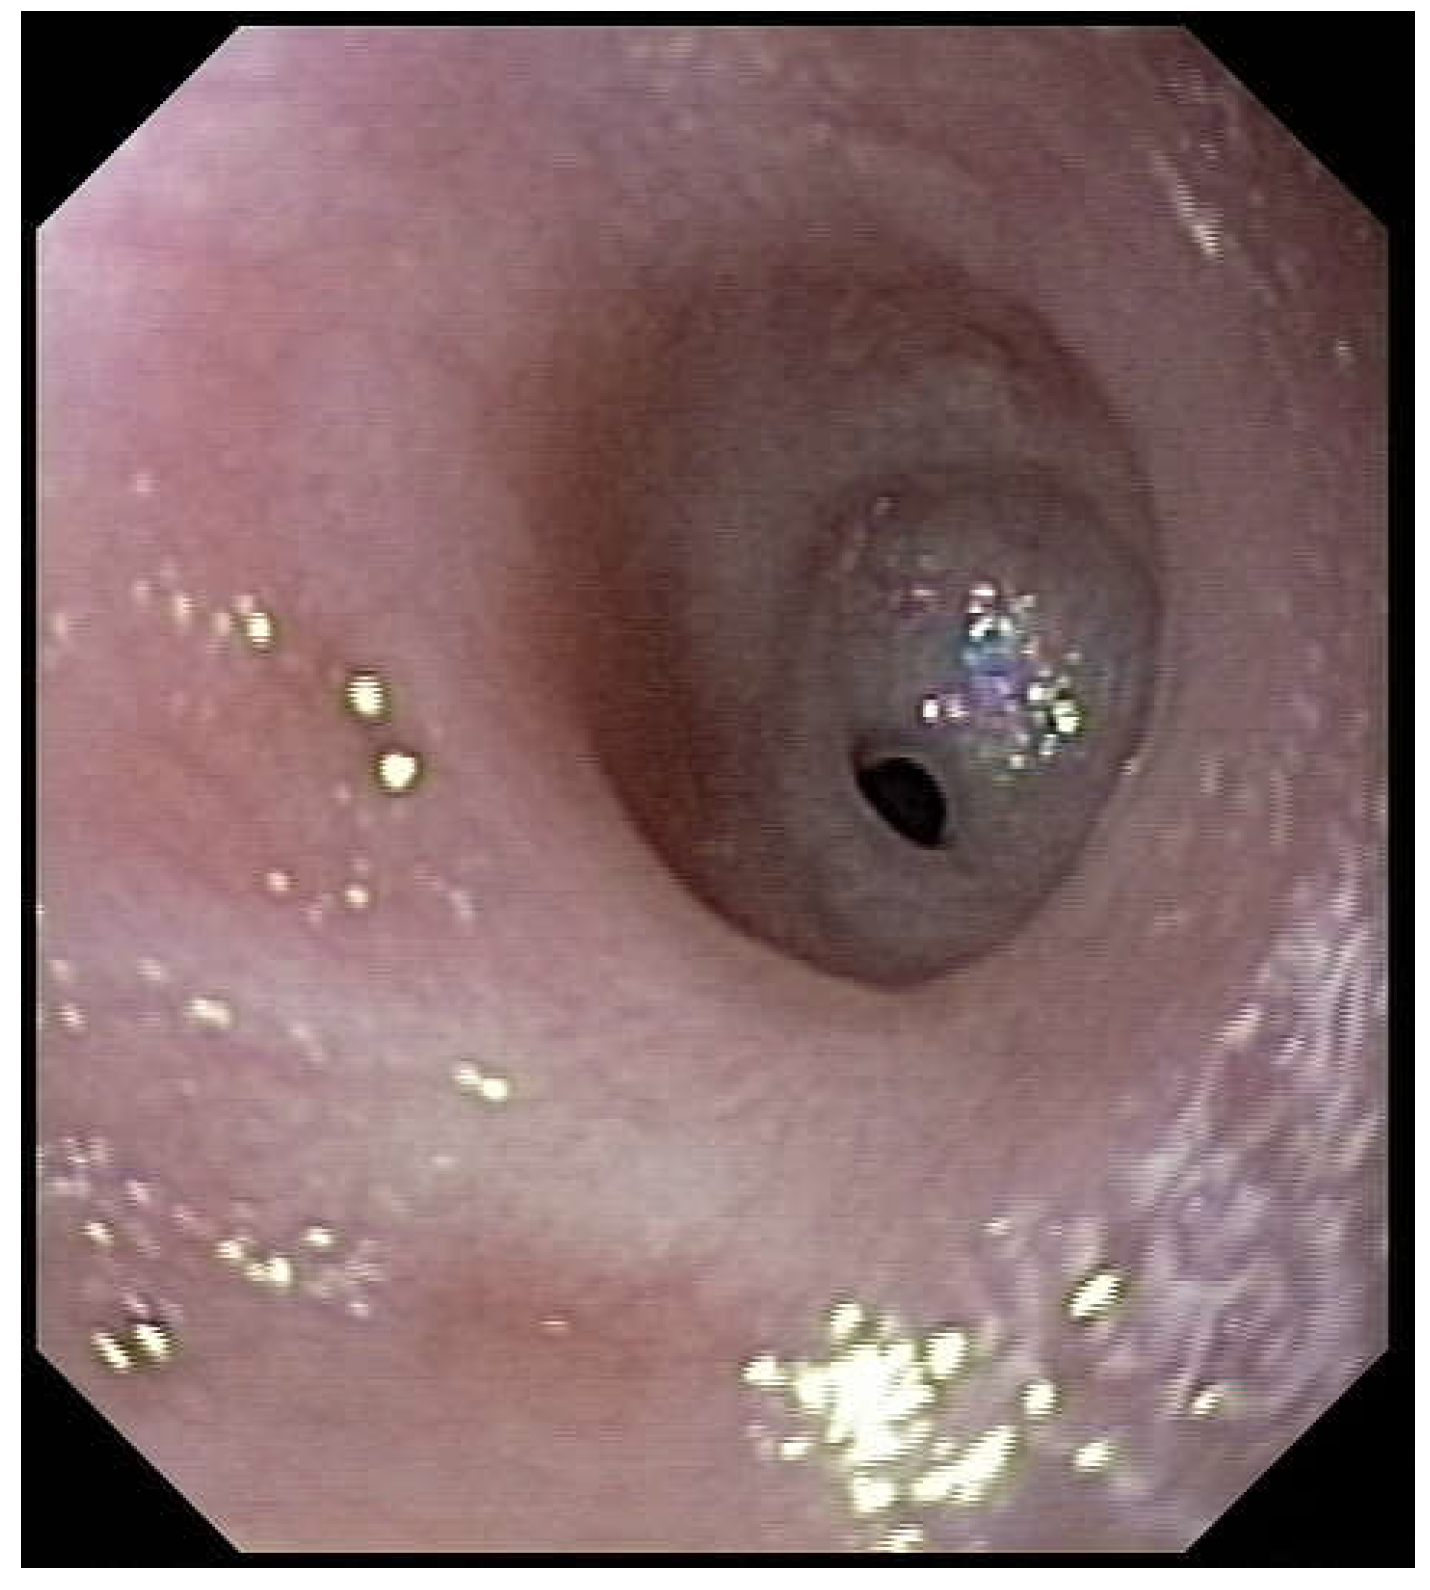

Figure 2). Intubation allows an endoscopic evaluation of the grade of esophageal and pharyngial stenosis and mobility of the vocal cords (

Figure 3). This evaluation is done with our Ear-Nose-Trachea (ENT) colleagues and eventual tracheotomy is discussed for very high stenosis of the larynx without residual damage to the esophagus.

A preoperative evaluation of the oropharynx and larynx must be done before surgery, as associated lesions are not unusual (15%) [

1]. It should include the examination of vocal cord movements during spontaneous breathing under anesthesia, as vocal cord will play an important role when eating during the recovery period.